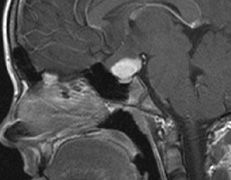

- Schwannomas most commonly affect the fifth cranial nerve (CN), but

any cranial nerve may be affected. In contrast to vestibular

schwannomas (CN VIII), these typically do not grow large.84,90 Vestibular schwannomas (acoustic neuromas) are the classic finding

in NF2 (Fig. 7). The risk for malignant transformation is low, but may be higher

with radiation exposure.84,94

- Meningiomas are most likely to affect the spinal cord and supratentorial

part of the cranium.84

- Other tumors: low-grade ependymomas and gliomas may affect the cervical

spine and Brainstem (Fig. 7).84